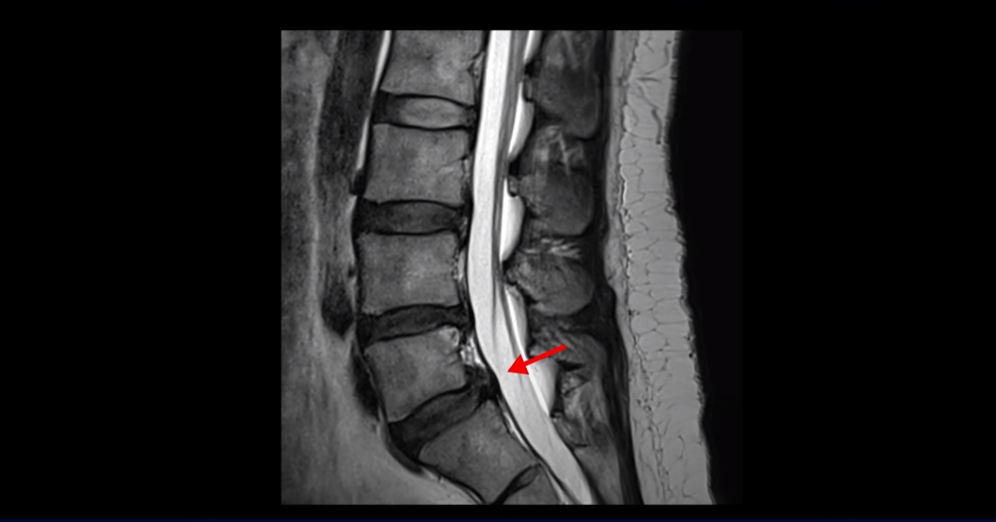

무거운 물건을 들다가 갑자기 심한 허리 통증 및 오른쪽 다리 방사통과 함께 오른쪽 고관절, 무릎, 발목에 운동 마비가 발생했습니다. 왼쪽 다리와 발은 움직이는데 오른쪽 다리와 발은 움직임이 전혀 없습니다. 문제는 이분 MRI를 보면 디스크 탈출이 심해 보이지 않습니다.

가운데 우측으로 파열도 아닌 돌출 정도의 탈출만 있습니다.

추간공도 충분히 열려 있는 상태입니다.

누가 봐도 이 정도 디스크로는 심한 마비가 올 수 없는 상태입니다. 근전도도 정확하게 마비의 원인이 허리에 있다고 설명하지 못했습니다. 그러니까 어느 병원도 수술을 자신 있게 하라고 얘기를 못 하고 마비가 왔으니까 그래도 수술을 해 보는 게 낫지 않겠냐고 얘기합니다.